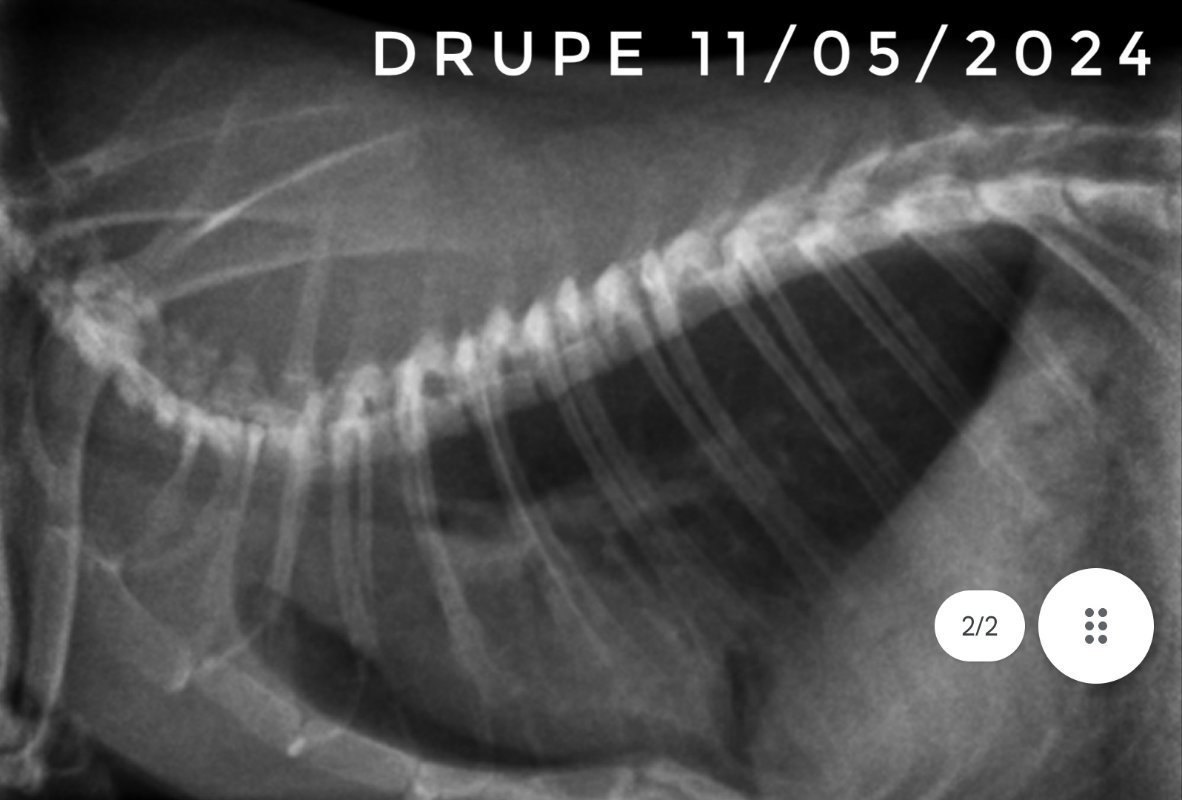

Et voici les dernières radios de Drupe. On est donc normalement sereins, les poumons ne sont pas parfaits, mais on est sûrement sur des cicatrices. Maintenant, il lui reste à passer l'étape de la castration et normalement ensuite il sera tranquille niveau soins vetos ^^

Chez les autres bébés qui ont survécut et qui ont arrêté les traitements en février, un seul a été provisoirement remis sous traitement, et c'est suite à des petits éternuements sur toute la troupe, qui n'ont pas commencés par lui, et il n'a pas été particulièrement touché. Ils ont tous des poids corrects pour des ratons de leur âge, sauf Drupe qui est plus petit mais il prend progressivement quand même.